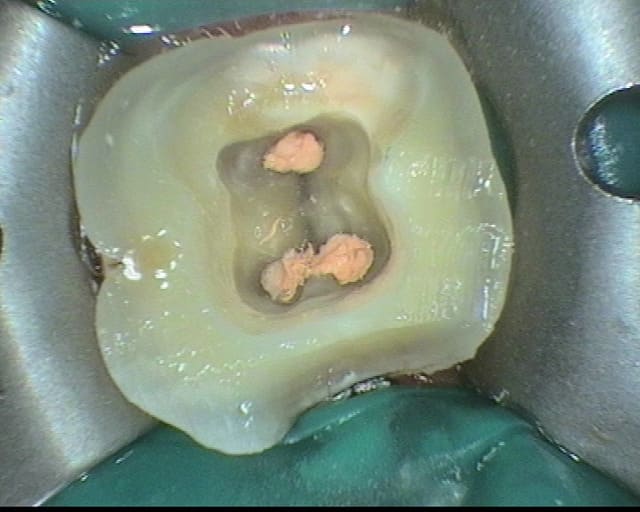

pour répondre à la question initiale du post, un cas de molaire dépulpée non couronnée.

Mise en place d'un cvimar (fuji II lc) en recouvrement de l'entrée canalaire puis onlay Empress collé.

Patiente de 21 ans.